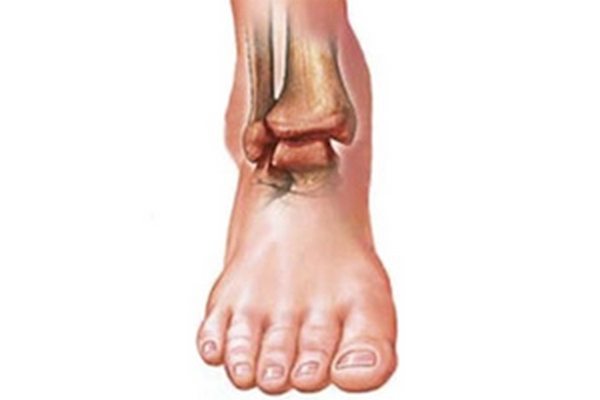

Ограничение подвижности стопы, сильные, пронизывающие или тупые давящие боли, отек — ведущие симптомы артрита голеностопного сустава. Патология развивается из-за чрезмерных физических нагрузок, малоподвижного образа жизни, расстройства работы иммунной системы. Заболевание 1-2 степени тяжести хорошо поддается консервативной терапии. А при обширном поражении хрящей, костей голеностопа требуется хирургическое вмешательство.

Острый артрит клинически проявляется сильными болями, отечностью, скованностью движений. Кожа в области голеностопа краснеет, припухает, становится горячей на ощупь.

На этапе ремиссии хронический артрит почти не проявляется клинически. Изредка возникают дискомфортные ощущения при перемене погоды или переохлаждении. А при рецидивах отмечаются острые боли в стопе, ограничение подвижности, отек.